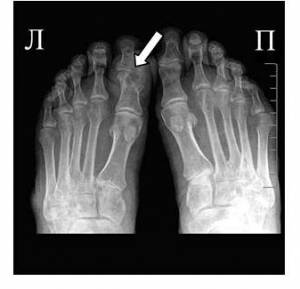

На фото симптом «пробойника» на кости первого пальца ноги

- Рентген-диагностика воспаленных суставов.